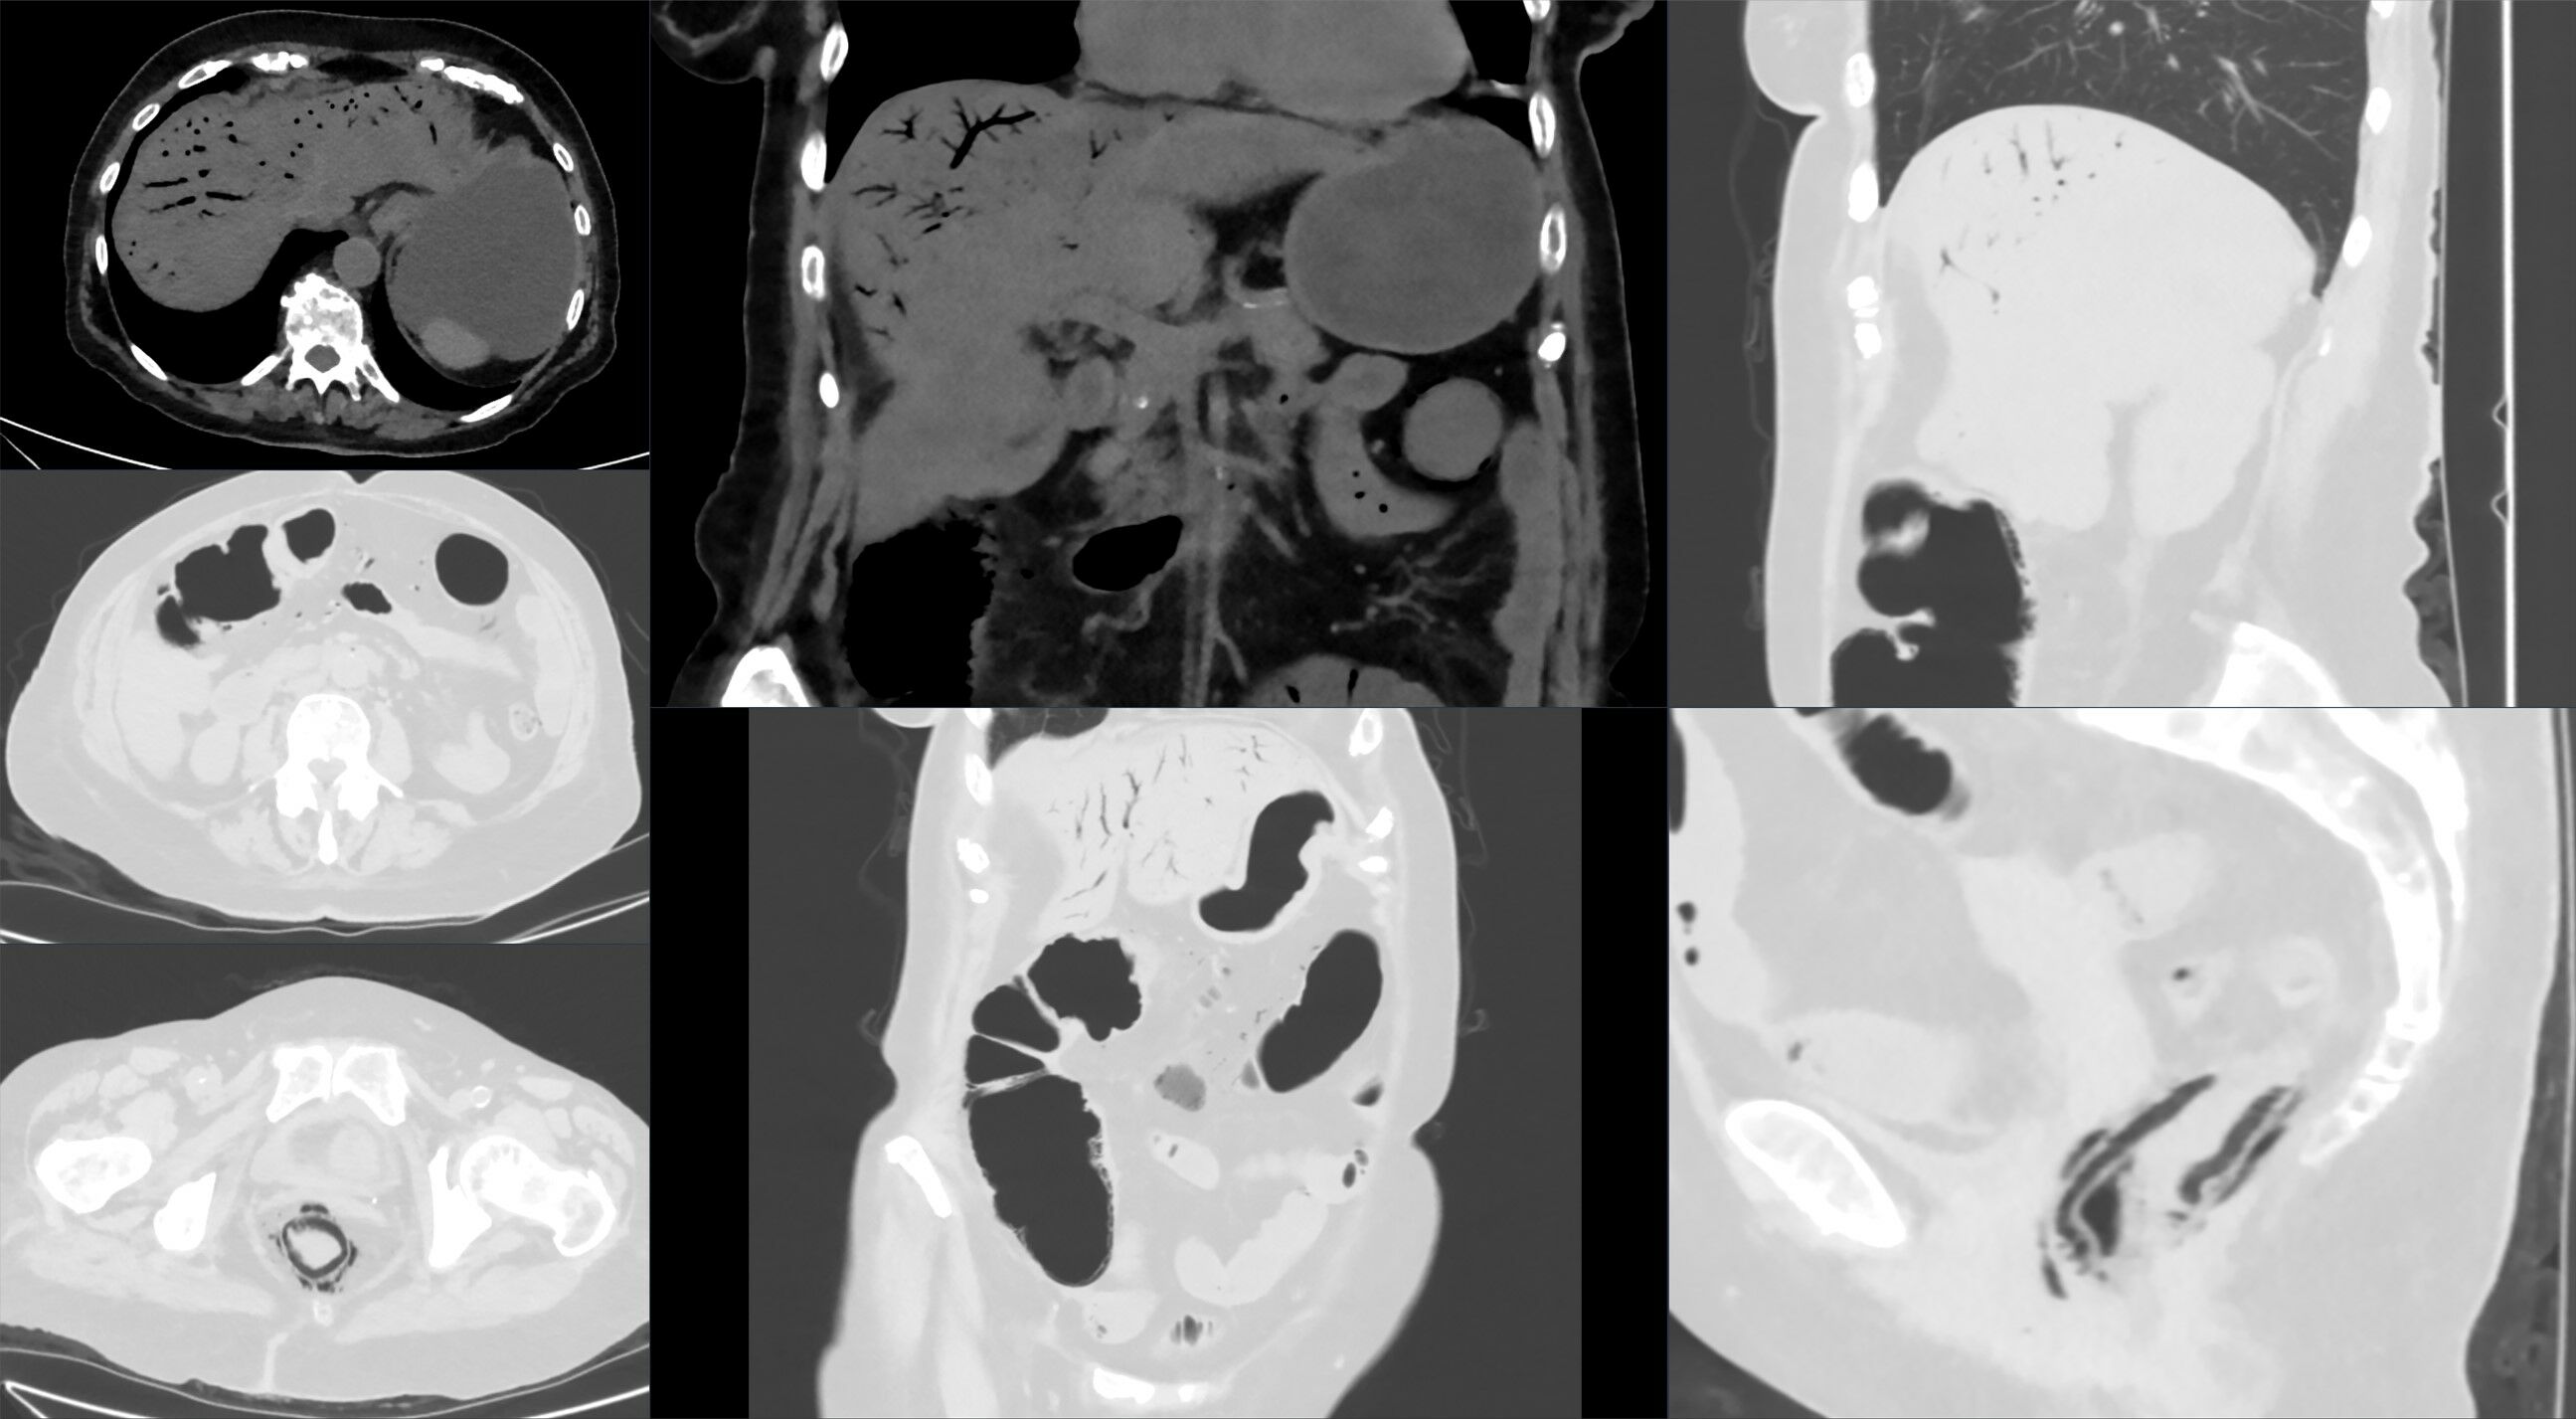

일반 X-ray는 종종 정상 소견을 보이거나 비특이적인 소견을 보일 수 있다.[28] 컴퓨터 단층 촬영(CT)이 자주 사용된다.[29][30] CT 스캔의 정확도는 소장 폐쇄(SBO) 유무에 따라 달라진다.[31]

CT 스캔 초기에는 장간막 부종, 장 확장, 장벽 비후, 장간막의 선상 음영, 인접 장기 경색 등이 나타날 수 있다.[29][32] 색전성 급성 장 허혈에서는 CT 혈관 조영술이 진단 및 치료에 매우 유용할 수 있다.[3]

장관 괴사를 나타내는 후기 소견에는 장벽 내 가스, 문맥 가스, 복강 내 자유 공기 등이 있다.[29]